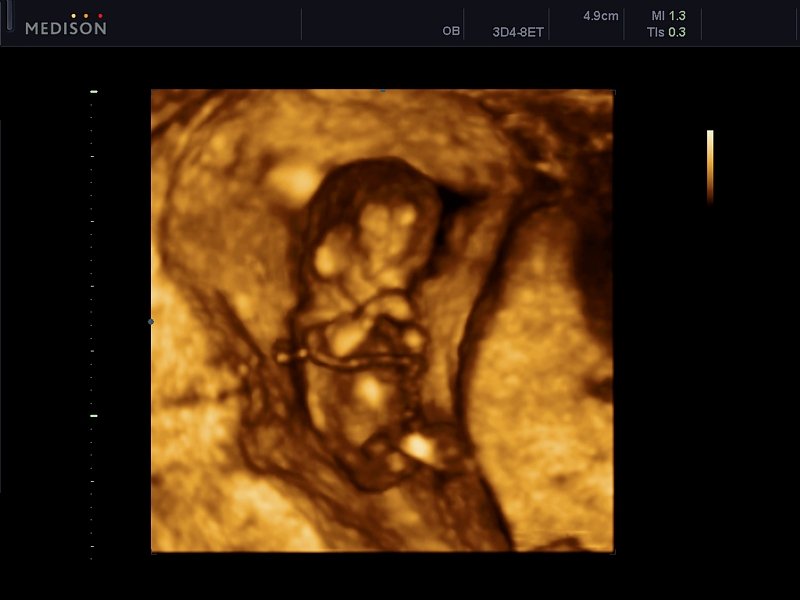

[RU] Ultrasound image №608: Fetus (12 weeks of gestation) in 3D mode (3D probe 4-8 MHz).

Echogramm was received by ultrasound scanner Accuvix-V10 (out of production).